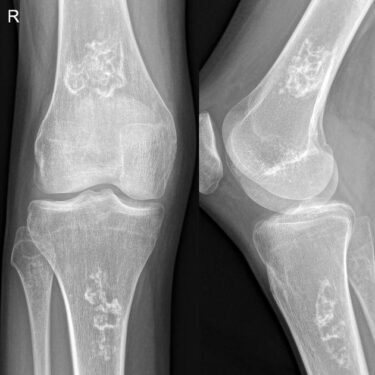

سکته استخوانی

۱۸ آبان ۰۴